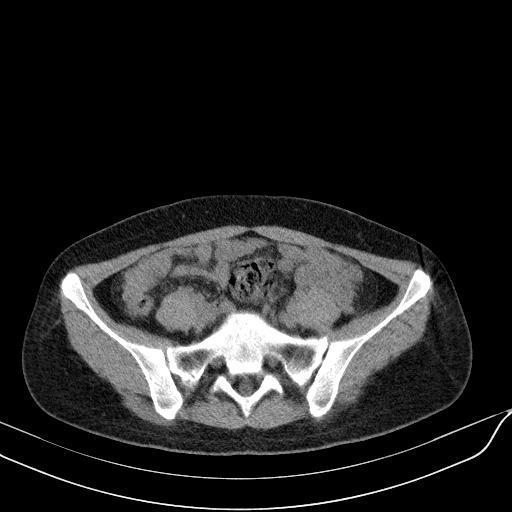

标题: CT23965:无外伤史,下腹痛 [打印本页]

标题: CT23965:无外伤史,下腹痛

肠道未准备,继续往下扫,乙状结肠占位不排除。建议钡灌或结肠镜检查。

乙状结肠占位不排除

扫描时应做肠道准备,口服稀释造影剂。

回肠间质瘤?

肠道肿瘤,建议行钡剂灌肠检查。